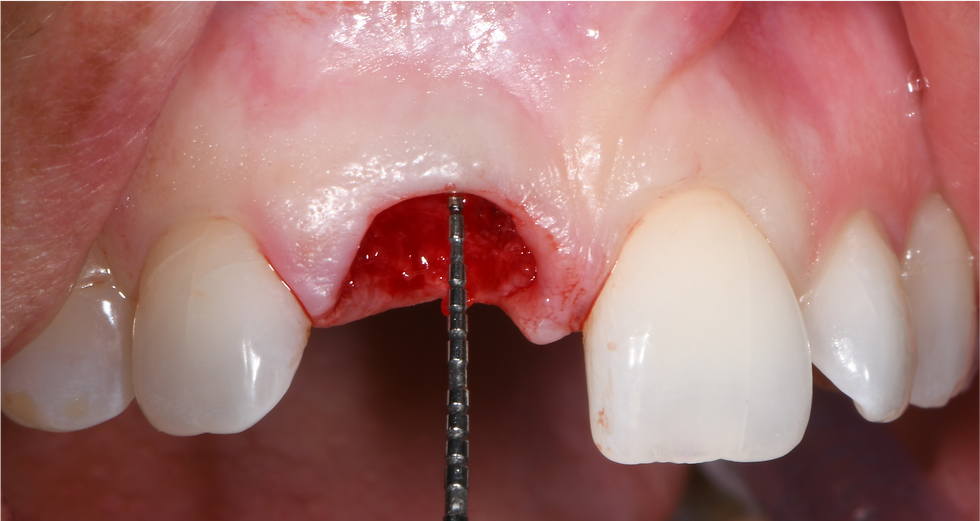

Extraction of the hopeless element

Planning of the prosthetic-guided surgery